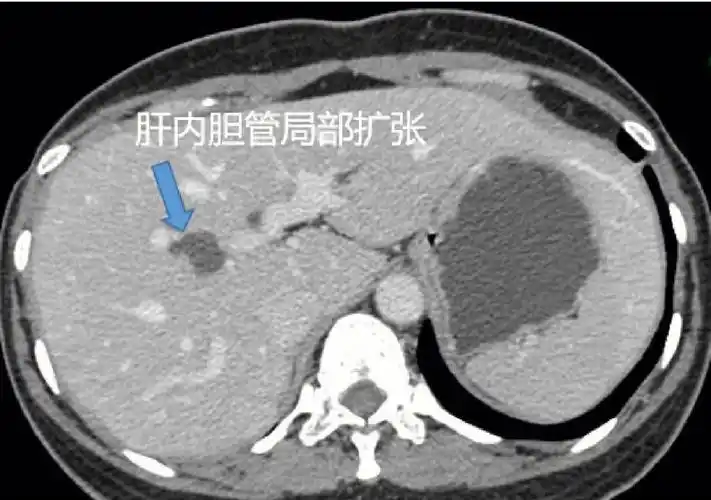

医学影像学 #临床 #医学肝内胆管局限性扩张,远端未见扩张,胰头部